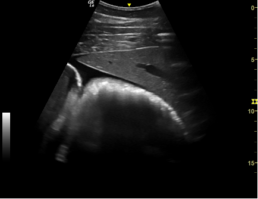

Leber (unauffällig-mittig im Bild), Dickdarmausschnitt (unauffällig) und vermehrt freie Flüssigkeit